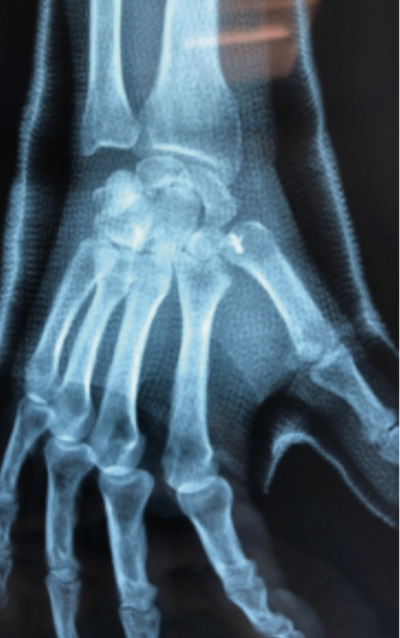

C’est l’arthrose de l’articulation reliant 2 os de la main appelés trapèze et premier métacarpien situés à la base du pouce au niveau du poignet. Cette articulation permet d’écarter le pouce des autres doigts et de le rapprocher de la paume de la main. L’arthrose associe l’usure du cartilage et la formation de petits fragments d’os gênant la mobilité d’une articulation appelés ostéophytes.

La localisation de la douleur oriente le diagnostic. Une simple radiographie de la main permet de confirmer le diagnostic.

– La trapézectomie: elle consiste à enlever le trapèze et le remplacer par un tendon pour soutenir le métacarpien.

• La prothèse trapézo-métacarpienne : elle ressemble à une prothèse de hanche miniature et en a le même fonctionnement.